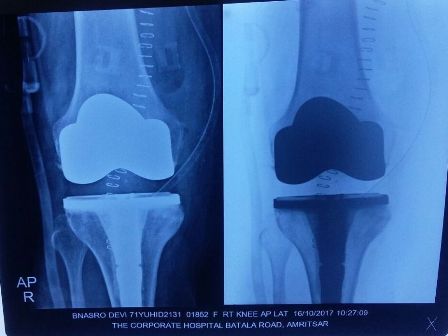

Patient : Mrs. Banarso Devi

Age / Sex : 71 yrs Female

Procedure : Bilateral TKR Done

• Total Knee Arthroplasty done with Tibial Stem.